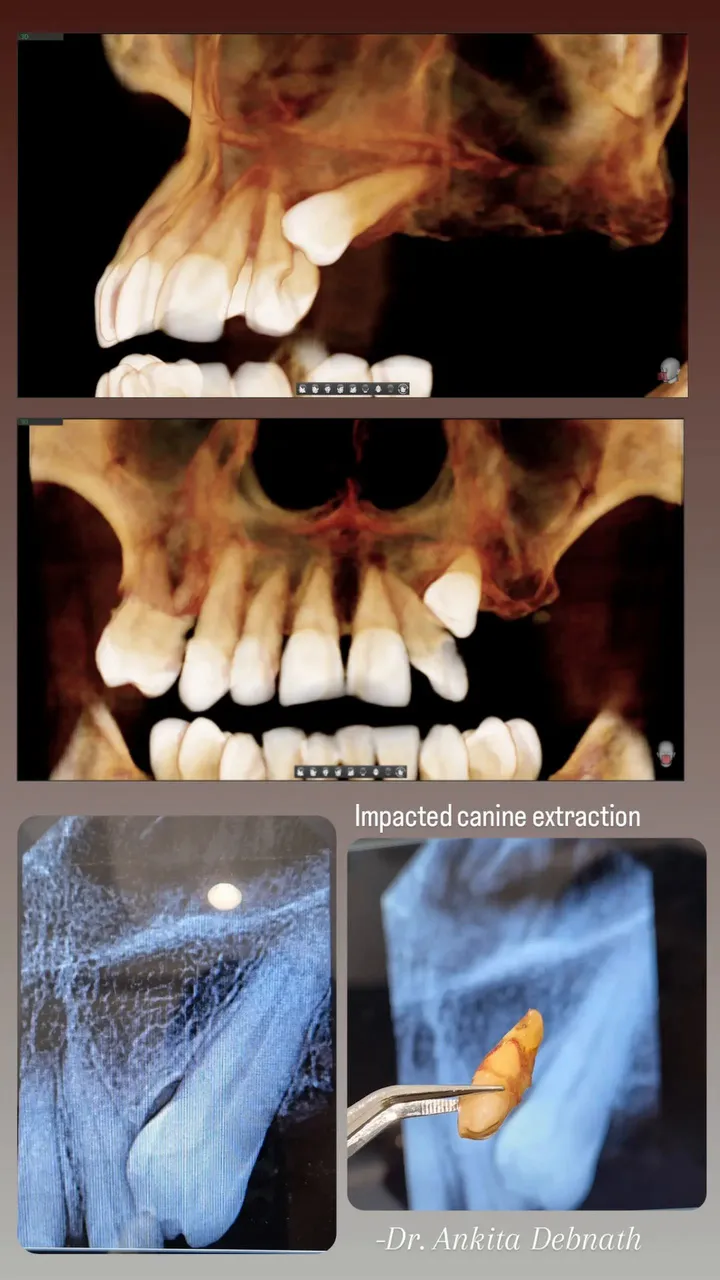

A BDS graduate from MS Ramaiah, Dr. Ankita Debnath holds specialized certifications in Implantology and Orthodontics. She is dedicated to providing modern, precision-driven oral healthcare using the latest clinical advancements.